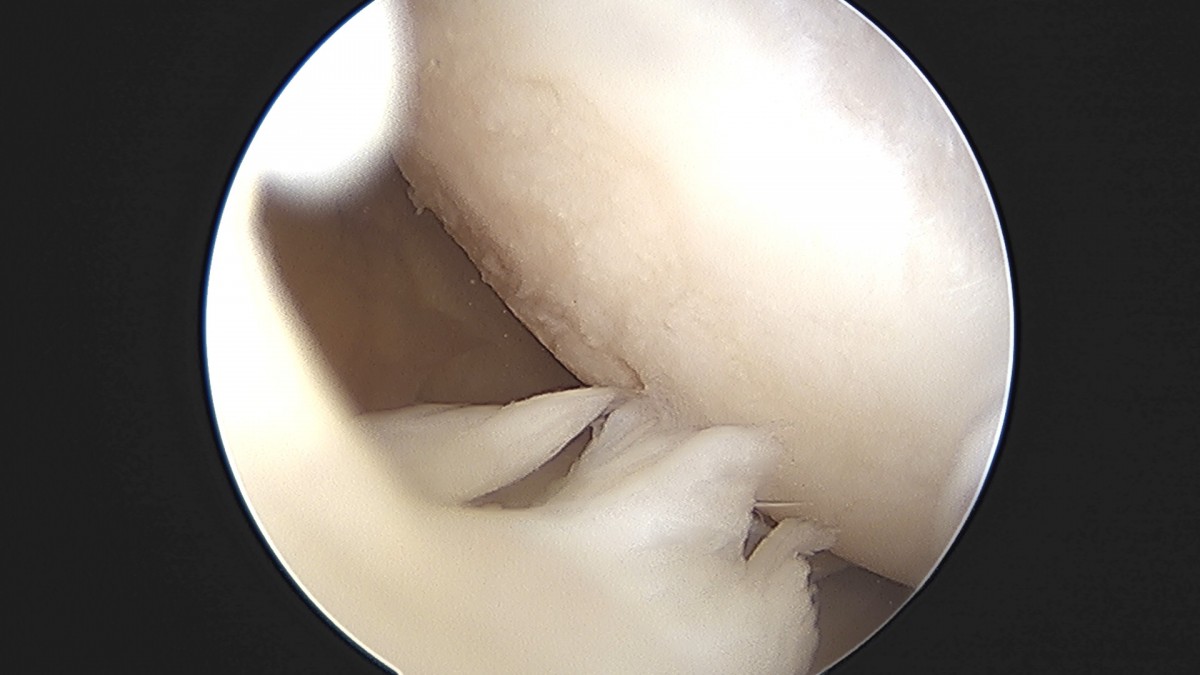

이재상원장님 무릎 낭종 제거술 김은O 환자

작성자 최고관리자 댓글 0건 조회 789회 작성일 25-09-16 15:20